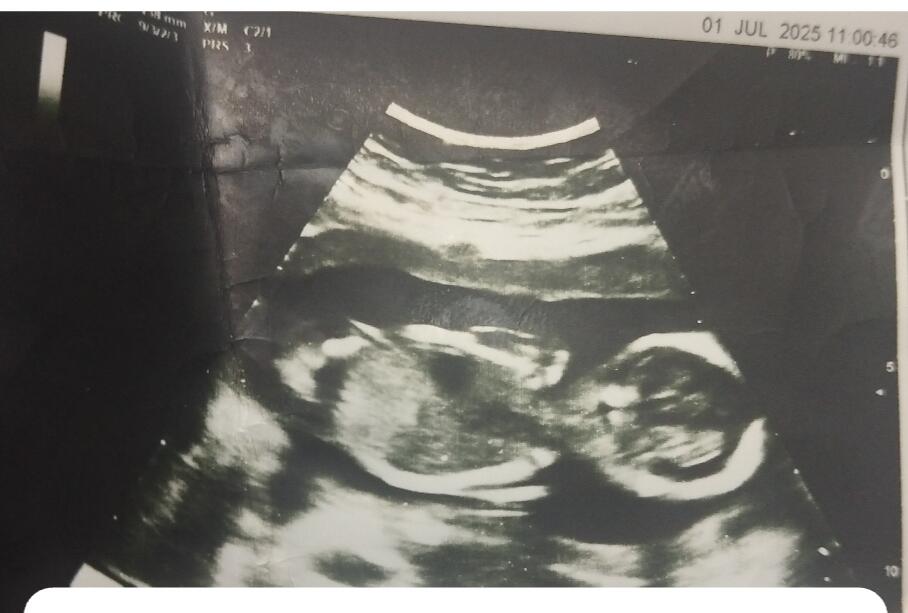

Ben kesenin fotosunu attım gözüküyor mu bilmiyorum sizce cinsiyeti bellimi

Kız gibi duruyor Allah sağlıkla kucağına almayı nasip etsin inşallah ![]()

Kız bu benim tahminim Hayırlı evlat olsun inşallah ![]()

Kız kesesi gibi duruyor sağlıkla gelsin ![]()

Sağlıcakla kucağına al canım. Bence erkek.

erkek gibi, sağlıkla gelsin bebişiniz.